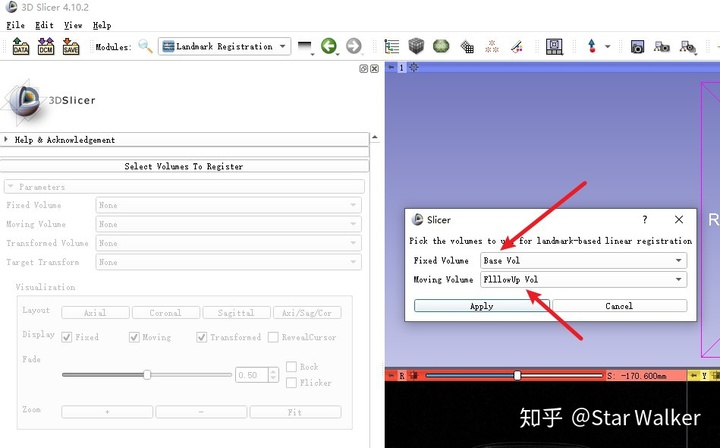

启动Landmark Registration

加载好数据,改好名称之后,就可与启动Landmark Registration模块,开始配准了。启动的操作路径如下图。

启动后,会提示指定要配准的固定图像和浮动图像,如下图所示。固定图像(Fixed Volume)指的是在配准过程中,保持不动的图像;而浮动图像(Moving Volume)就是那个在配准过程中,动来动去的图像。整个配准过程,其实就是一个始终不动,另外一个不断移动,直到找到最佳匹配位置。